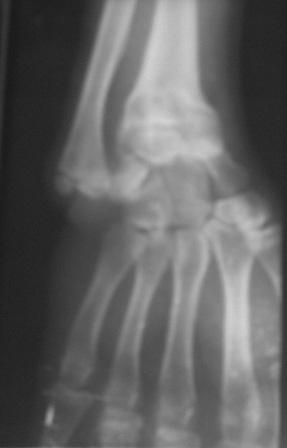

Доброго времени суток уважаемые коллеги! Обратился б-ной 16 лет.Травму получил 9-лет назад, перелом лучевой кости и надмышелковый перелом плеча. Имеется деформация л/з сустава типа лучевой косорукости, укорочение п/плечья, отсутствие локтевой девиации, cubitus vaus под углом 25 гр . Просит первоначально исправить деформацию л/з сустава и восстановить длину п/плечья. Наш план- остеотомия дистального метафиза лучевой кости, коррекция деформации и удлинение по методу Илизарова. Уважаемые коллеги, помогите советом! Можеть быть есть какие-то нюансы , или другие методы? Снимки прилагаются. С уважением Абдурашид.

С учетом возраста больного предлагаемая Вами тактика представляется оптимальной. Боковая ренгенограмма низкого качества, но кажется дистальный фрагментдостаточно короткий - надо постараться выполнить остеотомию точно на высоте деформации иначе трудно будет устранить угол.